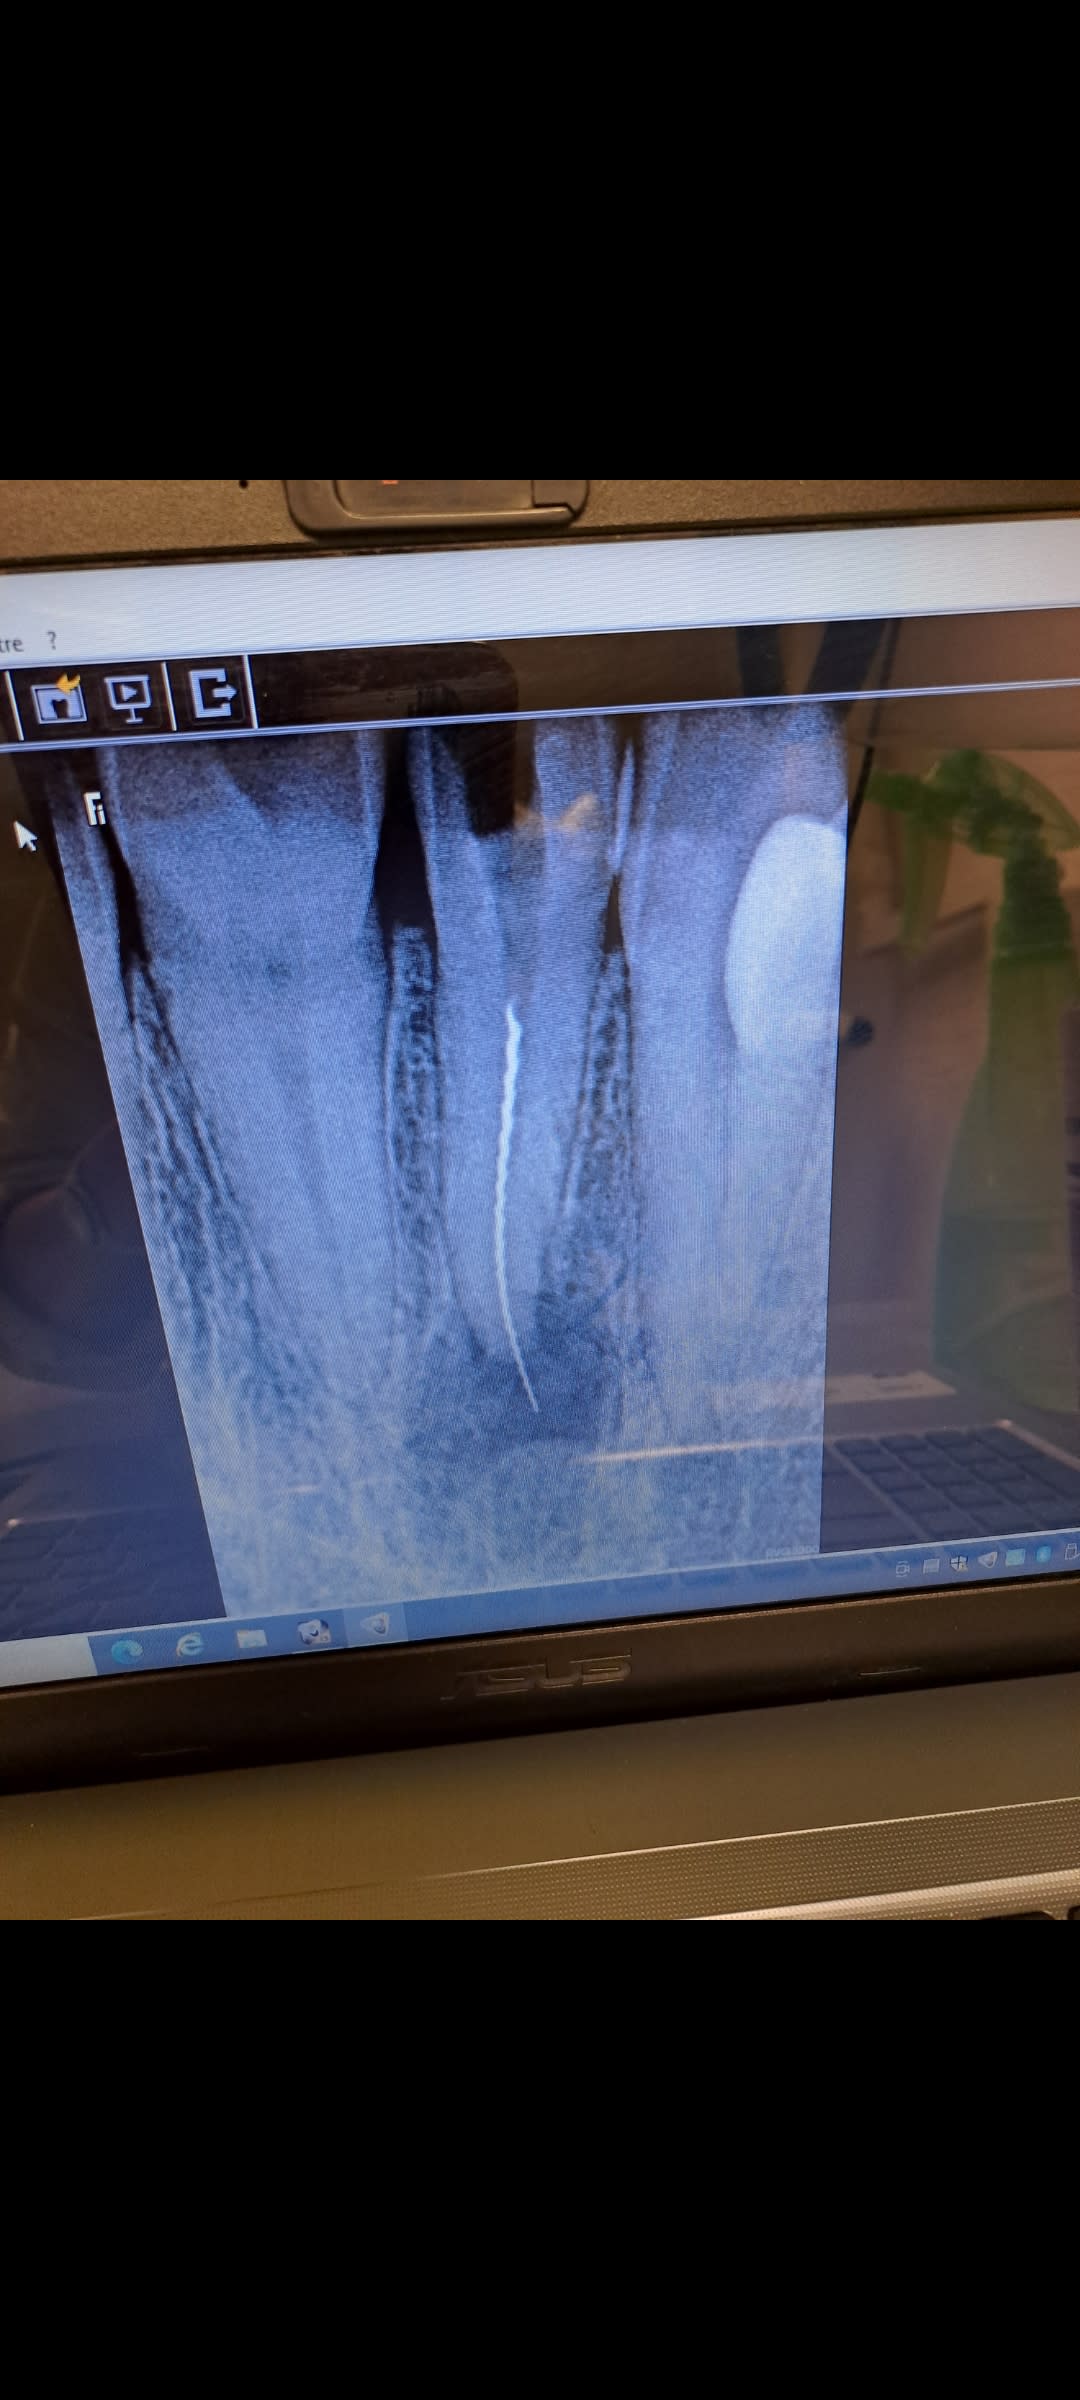

Bjr voilà il faut bien une 1ere fois dans notre carrière! La patiente est venue avec une dent necrosee 12 déjà sous AB , j'ai commencé l alésage et paf lime 15 cassée ! Je ne suis pas expérimentée pour tenter de la récupérer mais je ne veux pas refiler à un confrere ,je voudrais demander aux confrères expérimentés par quelle méthode commencee: comme il y a un début de granulométrie, je pense qu il faut éviter les US pour ne pas surchauffer ! Donc j'ai commandé plutôt le kit Endo Rescue et on se revoit la semaine prochaine

La 2e lime 15 peut passer à côté de la lime cassée.Jai enlevée la clamp pour faire ma radio .J ai laissé ouverte pour déjà le drainage

Sur la Rx, on dirait une lime H, ça visse guère ces trucs là, en tous cas c'est pas fait pour, certainement une des causes de la casse), contrairement à une lime K.

Moi je classe le cas de ttf en aléa, fracture avec léger dépassement. Et pour moi c'est une lime K, on voit bien les spires en tire bouchon, faudrait essayer de dévisser mais pas gagné vu la profondeur. Après la racine est bien large, on a de la marge pour passer à coté ou élargir pour mieux y accéder.

Bjr Gabzou, merci de ton encouragement. La patiente avait dejà un abces et une fistule quelques jours auparavant avant de me consulter et son medecin l avait mis sous AB, donc j ai laissé ouvert pour drainer . je la reverrai lundi . J ai pu faire du "bypassing" avec la lime 15 de chaque coté , donc je pense pouvoir elargir un peu et la recuperer au ...lasso. Je n aime pas trop utiliser la methode motorisée pour l instant pour eviter de l enfoncer plus; Je me suis exercée avec une dent au lasso ( vous pouvez en rire!) car je voudrais d abord me rattraper avant de le refiler à un confrere.....et j ai reussi à la sortir en tournant dans le sens antihoraire. Je croise les doigts pour le faire en situation réelle. Encore merci Gabzou pour ton soutien!

Et pour Gabzou, pour moi, c'est bien une lime H, Cf un vieux cliché, sur cette radio, le "tire bouchon", c'est la "H", elle est à droite. La "K" est à gauche.